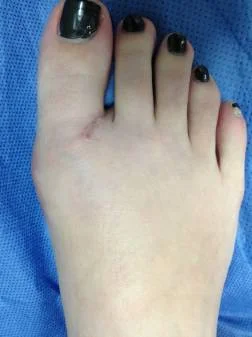

Paciente femenino de 32 años, portadora de hallux valgus doloroso en el pie derecho. Intervenida quirúrgicamente por el Dr Alberto Martínez Conde, practicandole cura operatoria con osteotomia del primer metatarso según técnica de Chevron y fijación con tornillo de Bold de 3.0 mm.

Postoperatorio 6 semanas